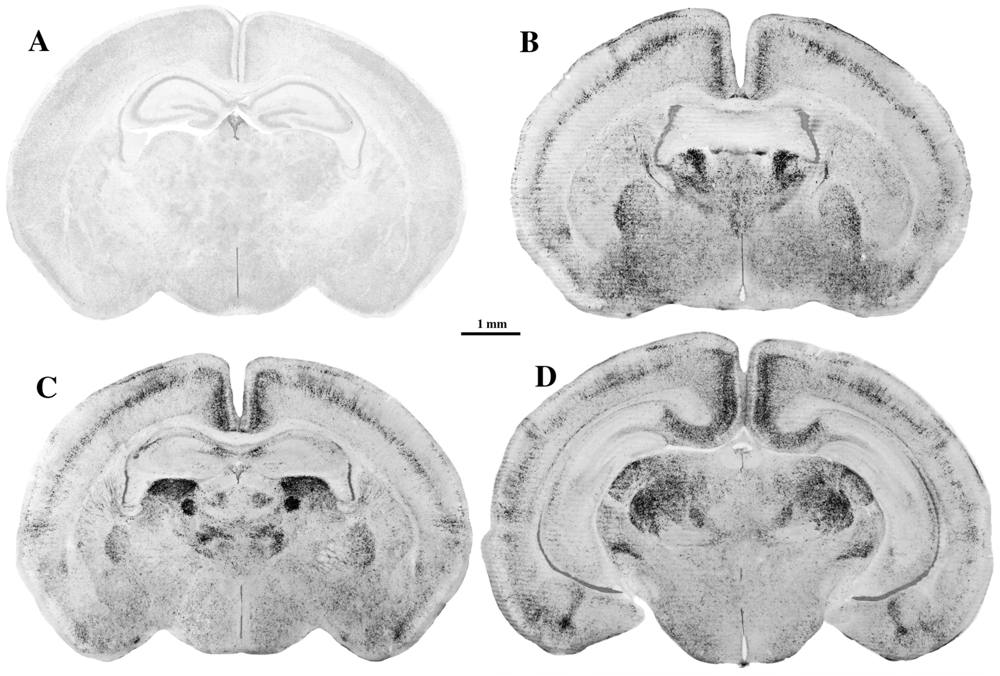

2.1. Neuroapoptosis

2.2. Oligoapoptosis